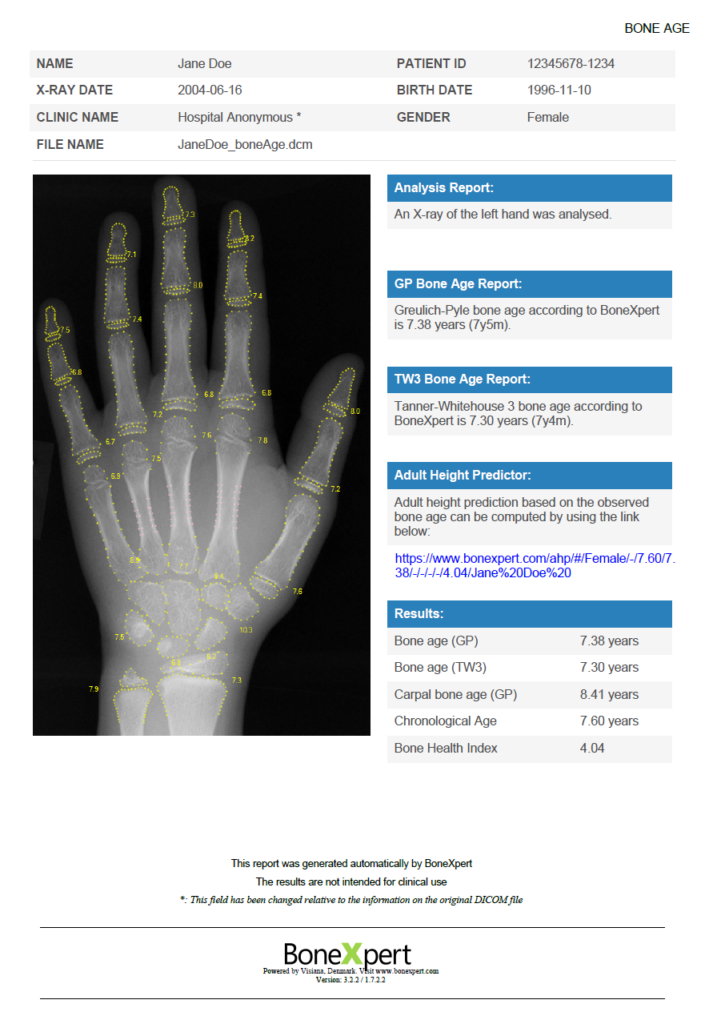

A single image can be analysed by dragging it into the browser or selecting it from computer files. Prior to bone age analysis on a BoneXpert Server, the hand image is anonymised. The user's personal information is securely stored on their computer, merging with the anonymised image once the payment is complete. An example of a completed analysis is provided below: